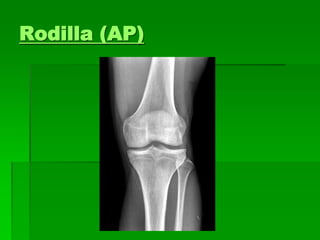

Rodilla frente (AP)

 Posición del paciente: Decúbito dorsal o

sentado sobre la mesa, la pierna extendida

sobre el chasis y rotación interna del pie.

 Rayo director: Puede incidir en forma

perpendicular sobre el vértice inferior de la

rotula o con angulación cefálica de 5 a 7

grados.

PROYECCION AP DE RODILLA

 EL PACIENTE se coloca en posición supina, con

la pierna completamente extendida.

 LA PELICULA 18 x 24. 24 x 30

 EL CHASIS: longitudinal.

 Colocar protección gonadal.

 EL RAYO: es perpendicular al plano, dirigido a

un punto medio de la rotula.(también 5º cefálico).

 ESTRUCTURAS MOSTRADAS: extremo distal

del fémur, el extremo proximal de la tibia y el

peroné. El espacio articular femorotibial, y las

carillas articulares de la tibia se observan en sus

extremos con una minima parte de su superficie.